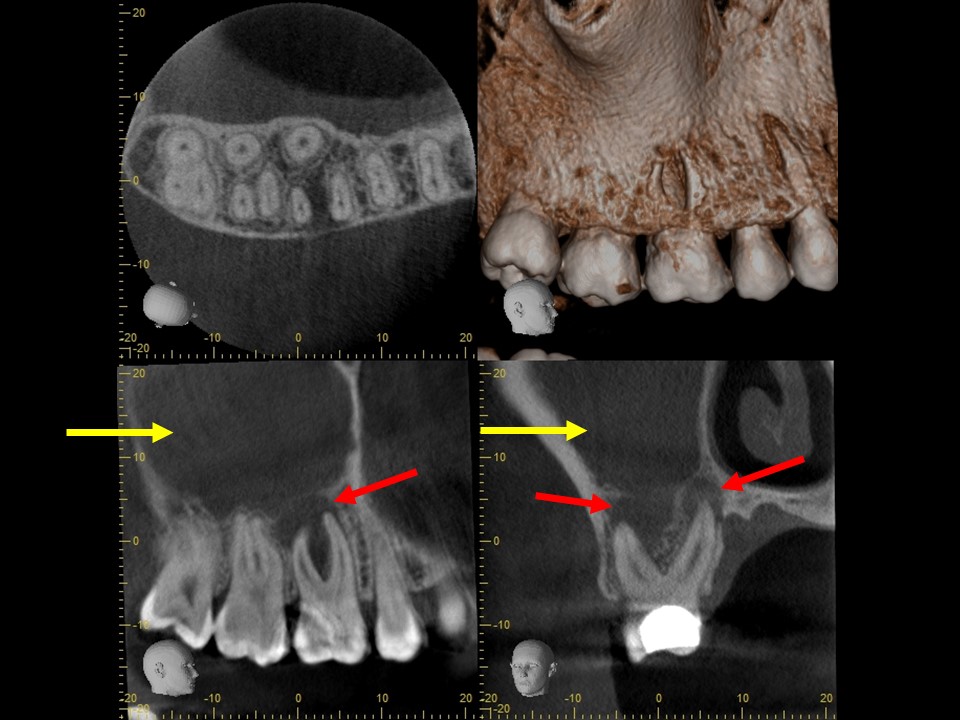

根管充填3か月後のCT画像にて、根尖病変および歯性上顎洞炎の予後を確認しました。根尖病変は顕著に縮小して骨の再生が見られ、上顎洞炎はほぼ治癒していました(下写真)。

根管充填3か月後のCT画像です。根尖病巣は顕著に縮小しており、骨の再生を認めます(赤矢印)。上顎洞の炎症も消退し、ほぼ正常像を呈していることが分かります(黄矢印)。病状が治癒傾向を認めるため、歯冠修復処置を行っていきます。

根管治療14か月後のレントゲンおよびCT画像です。術前にあった根尖部のX線透過像(赤矢印)ならびに上顎洞内のX線不透過性の亢進(黄矢印)は完全に消失し、根尖病変および歯性上顎洞炎は良好に治癒しているのが確認できます。